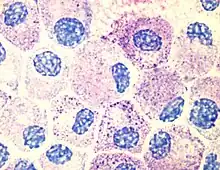

Mast cells

1. A resident cell of connective tissue that contains many granules rich in histamine and heparin.